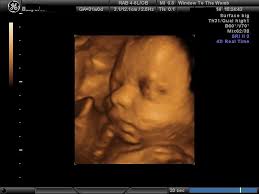

At this stage, the baby has put on some weight and filled out to make features more visible, yet still enough fluid in front of baby's face to obtain great images. I'm only at 31 weeks, but i had that 4d/3d u/s and yes, baby looked totally deformed. We just went yesterday at 31 weeks 4 days. In fact, it's quite similar to 4d ultrasound. Up to 32 weeks there generally still room for the baby to move. View images & learn more 30 week ultrasound The 4d ultrasound uses sound waves to create this moving image. Sofort kostenlos und ohne anmeldung anfragen

It is a fun time for the ultrasound as many times you will see movements like smiling, eyes blinking, hands moving, and many other movements. If you are having multiples this is also a good time to capture 3d pictures of the babies. At this stage, the baby has put on some weight and filled out to make features more visible, yet still enough fluid in front of baby's face to obtain great images. Your baby has to hold very still so that the high frequency sound waves have time to form around your baby's features. Snuggling cord at 18 weeks. The 4d ultrasound uses sound waves to create this moving image. Up to 32 weeks there generally still room for the baby to move. Baby impressions is an elective 3d 4d ultrasound imaging facility. At 18 weeks, your baby has mastered the art of yawning, along with hiccuping, which you may feel soon. You learn today about your baby development, prenatal care (doctor visits) and fetal ultrasound at 31 weeks. I'm only at 31 weeks, but i had that 4d/3d u/s and yes, baby looked totally deformed. Sounds like you have a very active baby! We require that all mothers have documentation of their prenatal care and most recent diagnostic ultrasound.

Come and see for yourlself. The best proof is our gallery of weekly 3d ultrasound images taken from 13 weeks and until up to 39 weeks. This page shows typical 3d ultrasound images from 11 to 36 weeks. All 3d ultrasound photos were taken in greenville sc at baby impressions. 18 week hd live/4d ultrasound. 3d/4d ultrasound march 31, 2021 | by kamrynlea has anyone gotten a 3d/4d ultrasound around 26/27 weeks? (so 31 weeks pregnant is the perfect time!) We do not perform medical ultrasounds. I have one scheduled and want to see some pics of what to expect!! At this stage, the baby has put on some weight and filled out to make features more visible, yet still enough fluid in front of baby's face to obtain great images. You're just dying to know what baby looks like inside your 31 weeks pregnant belly. Yawns, stretches, and even smiles are often captured in our 3d & 4d ultrasounds, and we look forward to sharing this miracle with you as well! Snuggling cord at 18 weeks.